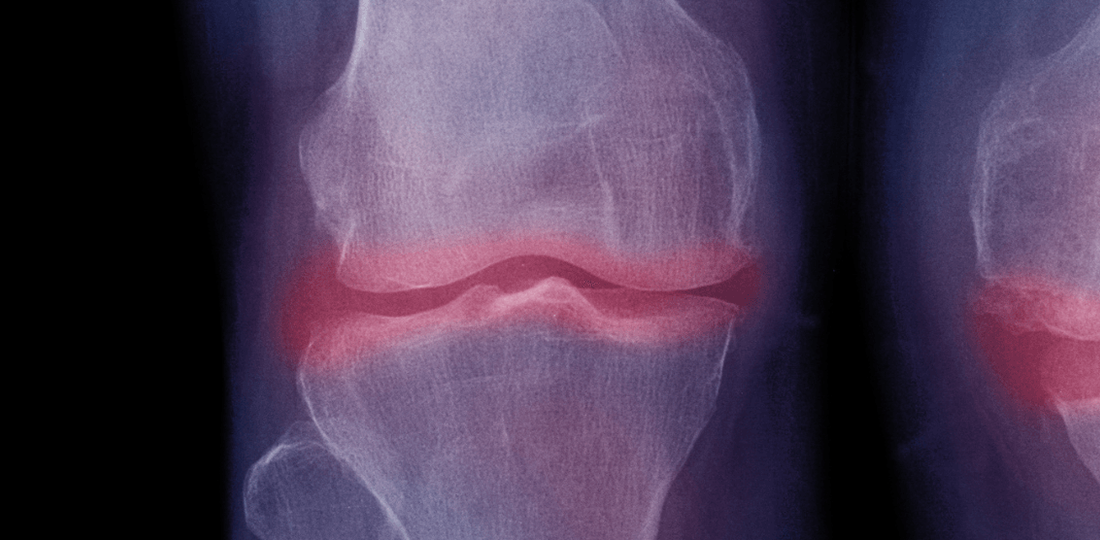

La artrosis se caracteriza por el desgaste del cartílago, el tejido resbaladizo que cubre los extremos de los huesos en una articulación. Sin el cartílago intacto, los huesos pueden rozar entre sí, causando dolor, inflamación y restricción del movimiento. Aunque la artrosis puede afectar cualquier articulación, es más común en las rodillas, caderas, manos y columna vertebral.